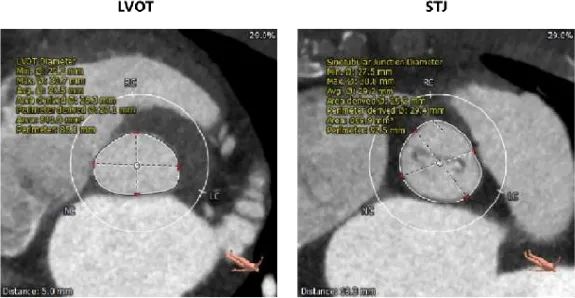

主动脉根部评估:

左冠开口高度12.0mm,右冠开口高度17.8mm,左冠高度较低,根据瓦氏窦内径和瓣叶长度综合判断,左冠存在较高堵塞风险;左室腔增大,心室壁未见明显增厚。

在术前评估阶段,首先通过心电图及超声探查,对患者心力储备、心脏电生理状况有了一个基本的把握,明确了患者自身的完全左束支传导阻滞,以及低 LVEF 情况。之后的 CTA 评估,通过瓣环上平面测量,提示了瓣叶较大冗长,上缘延展于 STJ 平面以上。于术前明确了冠脉极高闭塞风险,指示术中球囊预扩时,除常规 Balloon sizing 再次确认瓣膜型号外,还应当着重观察左冠灌注情况。

因此,在手术策略的制定上,我团队根据患者瓣环平均径及周长数据(24.0mm/79.1mm),基于高钙化患者 down size 方案及降低冠脉封堵风险考虑,选择了 26mm TaurusElite 瓣膜进行植入。术中采用 22mm TaurusAtlas 球囊预扩后,显示轻微腰征,造影无渗漏,左冠开口显影不明显,验证了术前判断。遂预埋冠脉支架,行烟囱支架置入术。